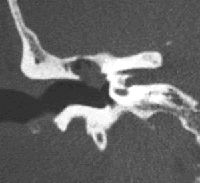

El colesteatoma és un tumor benigne de l’oïda, que afecta inicialment al timpà i als ossets (martell, enclusa i estrep). Està format per un cúmul de pell que creix de manera desordenada i progressiva.

El seu tractament és sempre quirúrgic, i consisteix en la timpanoplàstia, intervenció en la qual, mitjançant microcirurgia, s’extirpa completament el colesteatoma. El resultat (reeixit en un 90% de casos) serà sempre millor com més precoçment s’intervingui.

A més de l’extirpació completa del colesteatoma, la intervenció persegueix conservar al màxim l’audició existent, i si és possible la recuperació de la ja perduda, mitjançant la reconstrucció dels ossets de l’orella mitjana (ossiculoplàstia), encara que no sempre és possible.